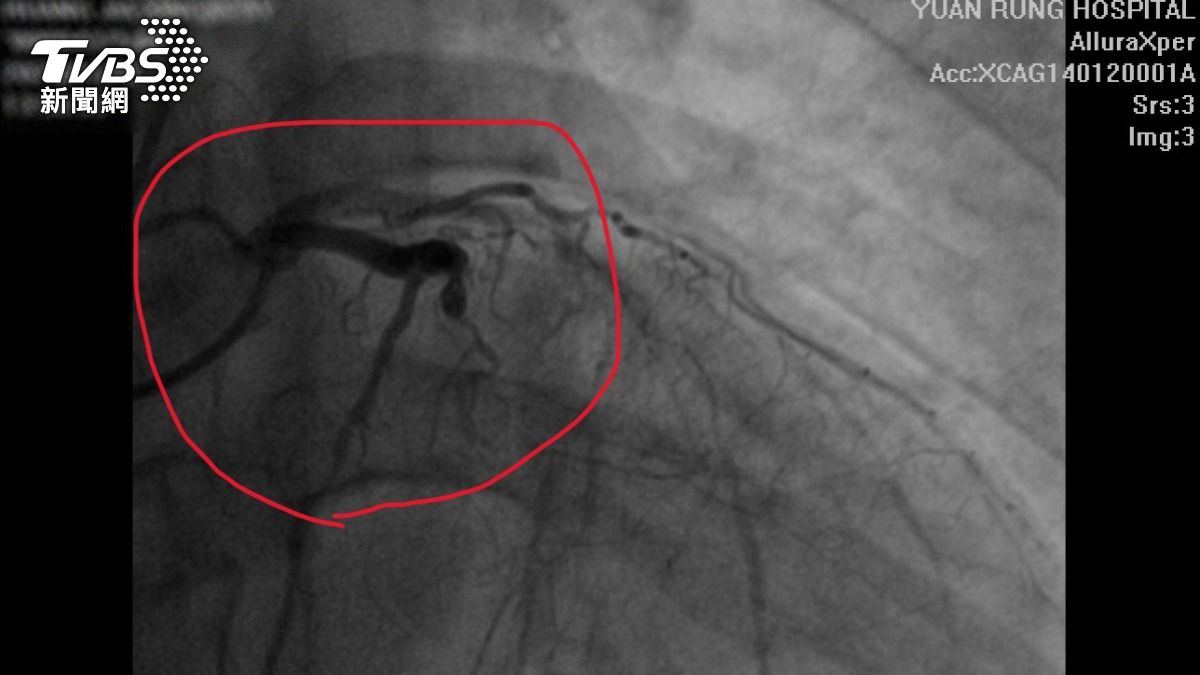

陳主任說,原本認為29歲男子血管問題機率很低,但檢查結果顯示,患者左前降支、左迴旋支及右冠狀動脈三條血管均嚴重阻塞,這正是導致心臟功能下降的主因。與其他因病毒感染導致心臟衰竭的患者不同,該名男子的心臟衰竭是由慢性血管阻塞所引起,可能在20多歲時因高血壓但未按時服藥,且常熬夜、飲食不正常等因素,造成血管已開始狹窄並逐漸惡化,最終導致心臟功能衰退。由於三條血管皆有問題,依據治療標準,特別是考量患者年輕,建議進行冠狀動脈繞道手術(搭橋手術),藉由自身動脈或靜脈移植血管,以繞過阻塞部位,恢復血流供應。